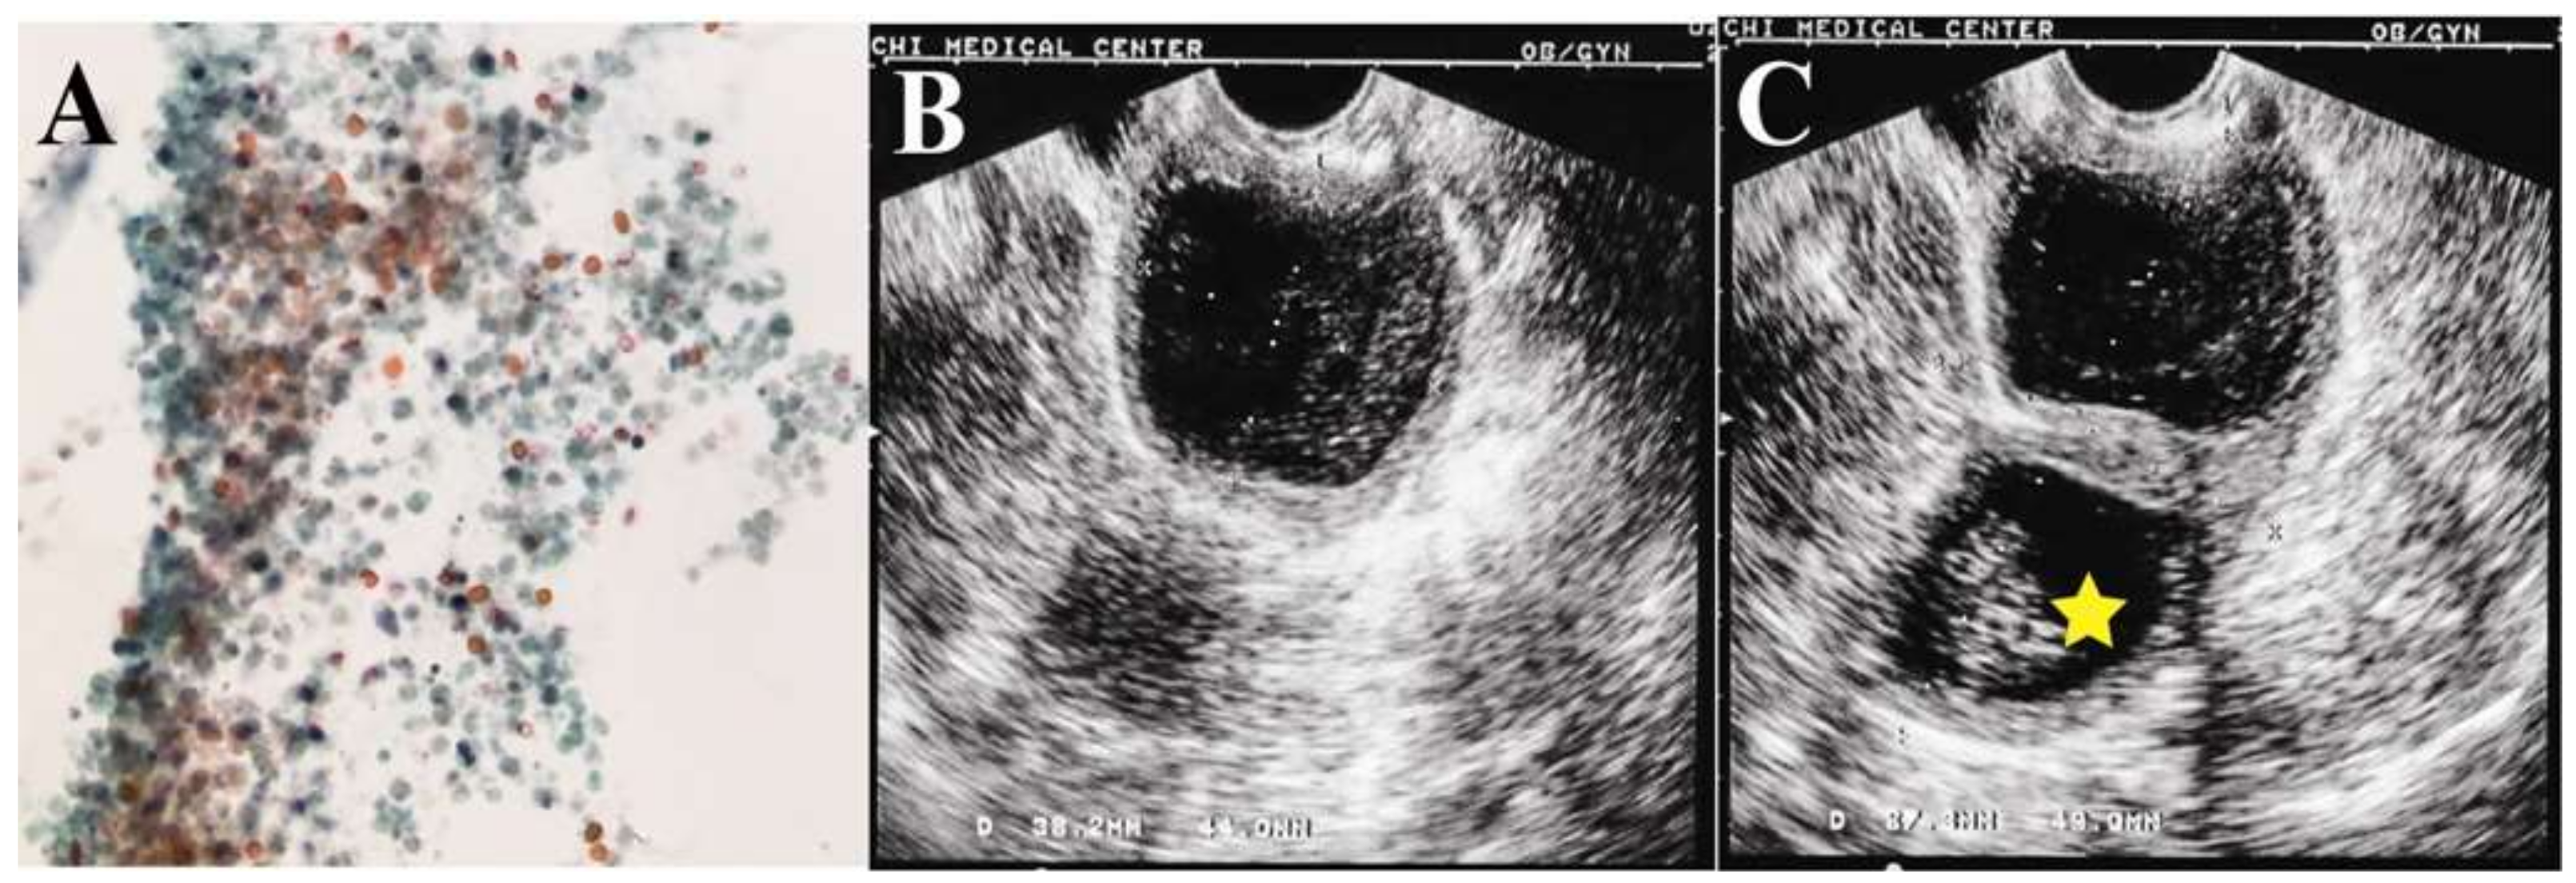

A 75-year-old nulligravida presented with underlying hypertension with well-controlled diabetes mellitus. She had visited our clinic for postmenopausal abnormal vaginal discharge five months earlier. Pelvic examination showed some watery brownish fluid with malodor in the vagina without visible cervical tumor. The cytology of the fluid showed some atypical cells (

Figure 1A). Trans-vaginal ultrasonography disclosed two distinct abnormal compartments in the pelvis: one near the probe resembled a homogeneous hypoechogenic hematometra (

Figure 1B), and another one near the left adnexa was a 41.3 × 59.4-mm cystic tumor with a solid component (23.8 × 24.3 mm) (

Figure 1C).